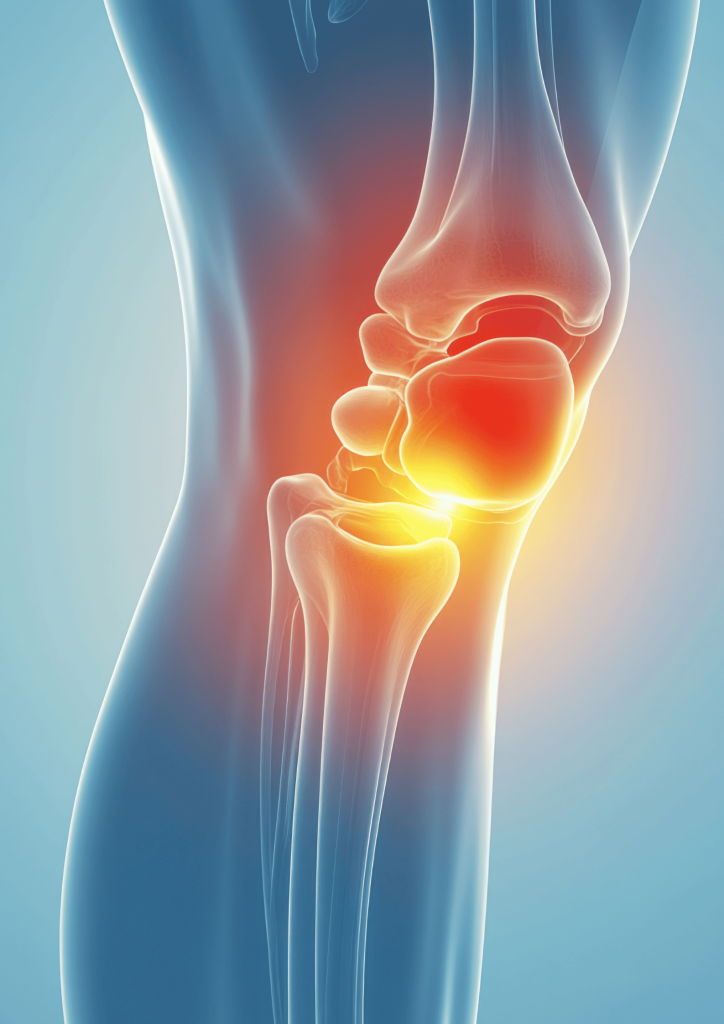

CIRURGIA DO JOELHO

LCA

RECONSTRUÇÃO DO LIGAMENTO CRUZADO ANTERIOR

A reconstrução do LCA visa restaurar a estabilidade anteroposterior e rotacional do joelho através de enxerto autólogo ou alógrafo colocado nos túneis anatómicos femoral e tibial. Indicado em instabilidade funcional, roturas completas e exigências desportivas elevadas. A técnica anatómica, associada à reabilitação estruturada, permite a recuperação da cinemática articular e o retorno seguro à atividade desportiva

Instabilidade patelo-femural

A instabilidade patelo-femoral resulta de desalinhamento patelar e insuficiência dos estabilizadores mediais, levando a translação lateral excessiva da patela.